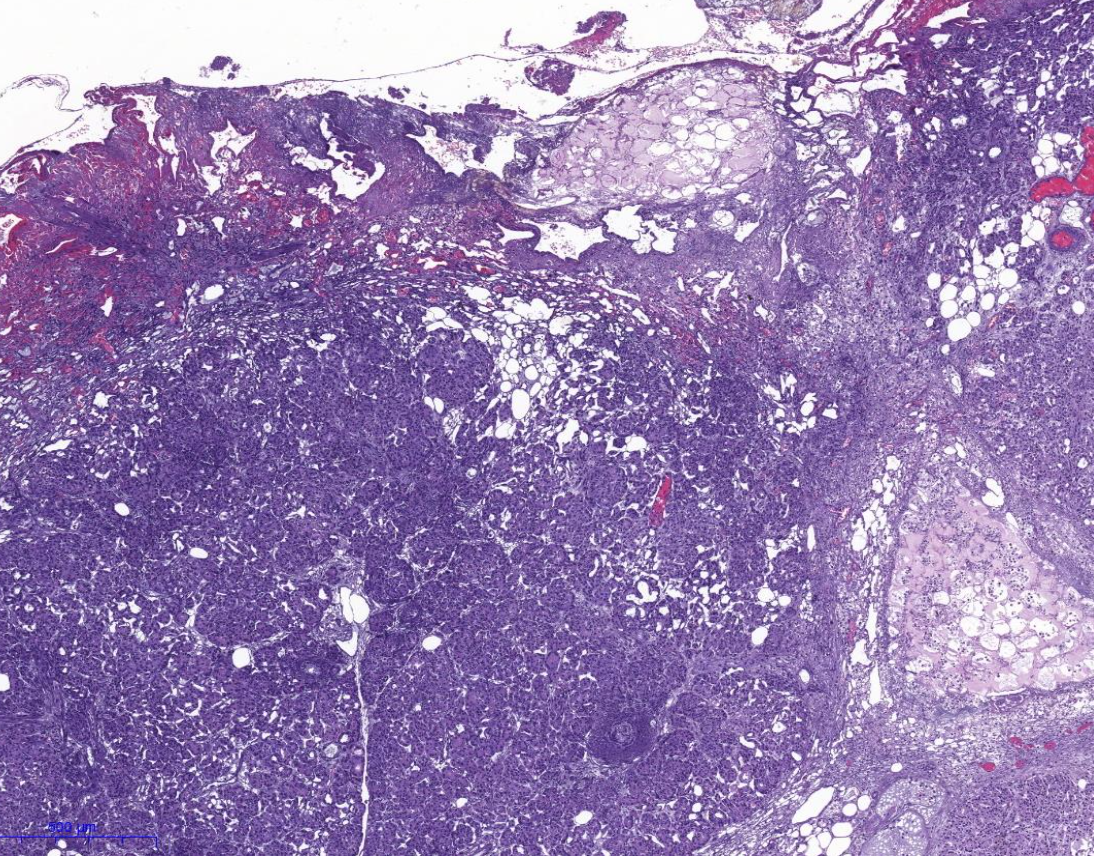

Diagnose?

Squamöse intraepitheliale Läsion (SIL)

Zervikale intraepitheliale Neoplasie (CIN)